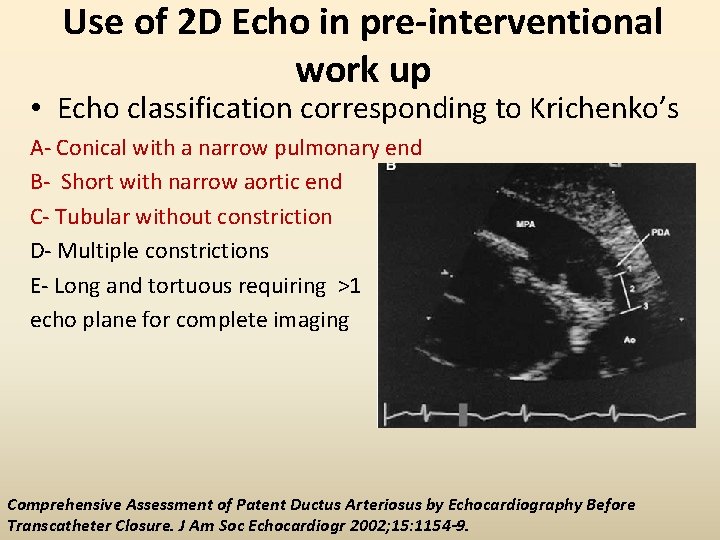

Use of 2 D Echo in pre-interventional work up • Minimum diameter (A) • Length (B) • Ampulla diameter (C) • PDA type

Use of 2 D Echo in pre-interventional work up • Echo classification corresponding to Krichenko’s A- Conical with a narrow pulmonary end B- Short with narrow aortic end C- Tubular without constriction D- Multiple constrictions E- Long and tortuous requiring >1 echo plane for complete imaging Comprehensive Assessment of Patent Ductus Arteriosus by Echocardiography Before Transcatheter Closure. J Am Soc Echocardiogr 2002; 15: 1154 -9.